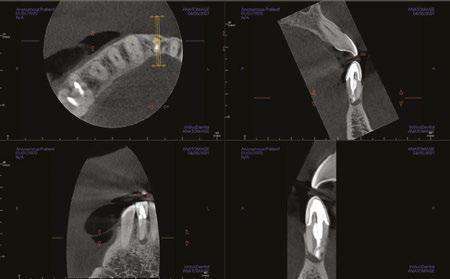

Judy McIntyre, DMD, MS Figure 1: Acutely curved and calcified buccal canal right under upper left premolar crown margin; valuable information for access and management. No. 9 also has a PARL, which was only incidentally captured Figure 2: Large PARL with destruction of the maxillary sinus floor and sinusitis as a result

About 10 years after completing residency, I opened my own practice and invested in a DEXIS CBCT. Initially, I only used it for apicoectomies and retreatments. In time, I began to realize how helpful it was for all my cases. With the 3D-scan information (Figure 1), I could have saved myself some humbling experiences and surprises. Endodontists hate surprises, and we really hate failures! Once I started using my CBCT more frequently, I was able to appreciate things that would have otherwise been intra-op surprises and plan for them prior to starting the procedure. The 3D data allows me to properly assess prognosis, determine the best course of treatment, and plan that treatment with a level of precision that is impossible otherwise.

Figure 3: Second maxillary molar with external root resorption (ERR) with incidentally captured ERR on the lower mandibular first molar as well. When there is one tooth with resorption, be suspicious of other teeth with resorption, especially on younger patients Figure 6: No PARL on PA film. Clear PARL on scan taken with medicament Figures 4 and 5: 4. Mandibular molar with a J-shaped lesion due to endo — not a vertical root fracture. Path of least resistance happens to be through a distal perio pocket, but this is an endo-perio lesion and not a VRF. Incidentally, a mucous retention cyst was captured in the sinus. 5. Healing after bridge removal and retreatment

Figure 7: Planned-for access with the scan info on this extremely calcified canine Figures 8 and 9: 8. Deep distal split with PARL. 9. Missed buccal canal; history of previous RCT, post, crown and apico Figure 10: Retreatment consultation. PA from GD Figure 11: Scan images show a previously existing strip perforation